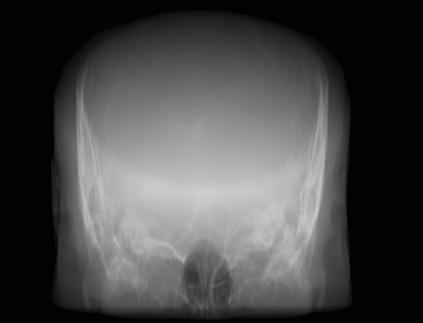

(a) Guide 𝑮𝑮\boldsymbol{G}

Refer to caption

(b) Input 𝑰𝑰\boldsymbol{I}

(c) Guidance map 𝑴𝑴\boldsymbol{M}

(d) Prediction 𝑷𝑷\boldsymbol{P}

(e) Ground truth

(f) Guide 𝑮𝑮\boldsymbol{G}

(g) Input 𝑰𝑰\boldsymbol{I}

(h) Guidance map 𝑴𝑴\boldsymbol{M}

(i) Prediction 𝑷𝑷\boldsymbol{P}

(j) Ground truth

Figure 2: Inputs and outputs of the guided filtering pipeline based on the WDSR network. T1 & T2 MRI pairs (a)-(e) and CT & MRI projection images (f)-(j).

In Fig. 2 and 4, exemplary input, output and label images of the pipeline are presented for both tasks. Additional super-resolved images for both network architectures with and without the guided filter can be seen in Fig. 3. The results show a consistently high quality over both, the tomographic and the projective domain, as well as both tasks. Corresponding quantitative evaluation can be found in Table I and II. For SR, the WDSR network, i.e., the designated super resolution network, performs consistently better for both datasets with and without the guided filter. Applied to the tomographic images, the approaches without the guided filter deliver slightly better quantitative results. For the projection images this difference diminishes and both approaches are on par. In the case of denoising, the approaches with the guided filter deliver a lower mean absolute error while the structural similarity is increased without it. Though, the measurable differences are only marginal. The results generated by the plain guided filter without the learned guidance map are numerically worse than the approaches empowered by the guidance map generator for all tasks. This observation is most prevalent when observing the results of the tomographic T1 and T2 Flair images for SR, while for denoising the results are closer to the deep learning-based approaches.

In general, the decrease in image quality metrics w.r.t. to smaller radii is much stronger for the tomographic T1 and T2 Flair images than for the projection images. We assume the reason for this to be the difference in resolution of both datasets. The projection images resemble the ground truth more closely from the outset when compared to the tomographic images as seen in Fig. 2(b) and 2(g), respectively. Consequently, more information has to be generated by the networks. As the guided filter is sensitive towards correlation between the input and guidance map the constraints on the applicable changes are more severe.